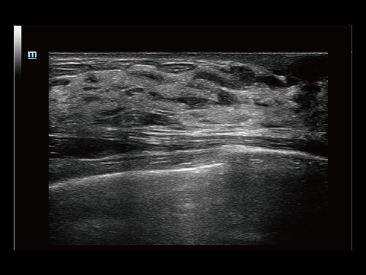

Since the company was founded, Mindray has been continuously exploring new ways to improve diagnostic confidence. Powered by the most revolutionary ZONE Sonography? Technology, Resona 7ŌĆÖs new ZST+ platform brings ultrasound image quality to a higher level by zone acquisition and channel data processing.

As well as the premium level image quality, Resona 7 also enhances clinical research capabilities with the revolutionary V Flow for vascular hemodynamic evaluation, and the most intelligent plane acquisition from 3D datasets for fetal CNS diagnosis. Combining the most intuitive gesture-based multi-touch operation and all the essential clinical features, Resona 7 is truly leading new waves in ultrasound innovation.